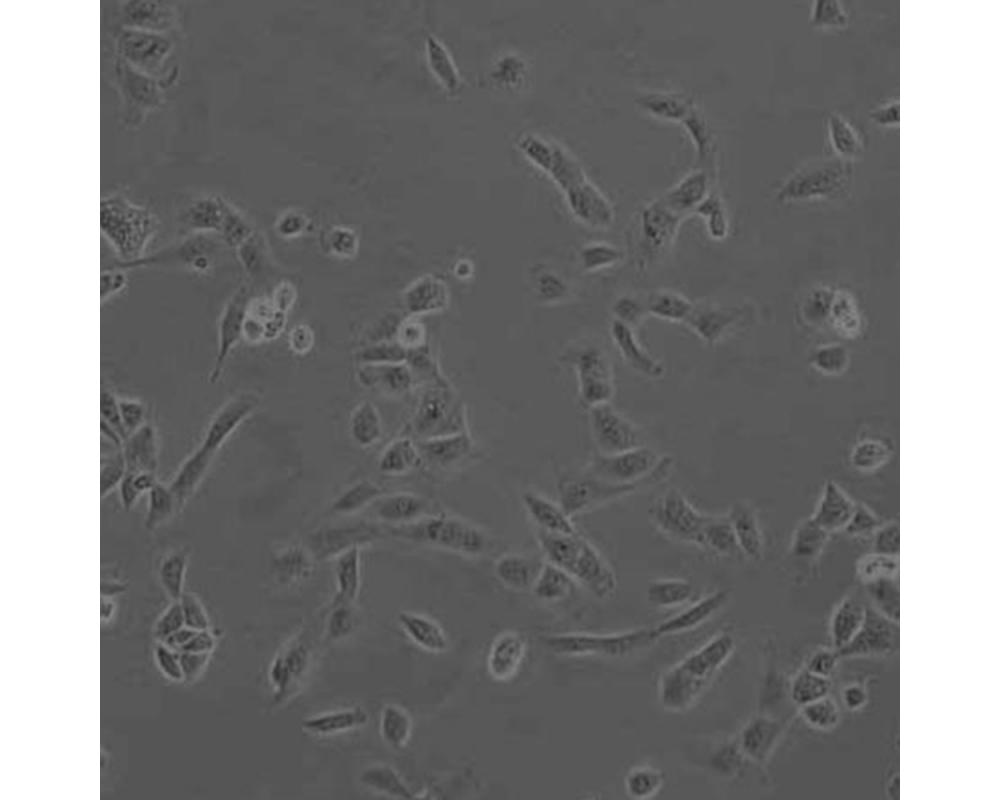

產品名稱 SNU449

中文名稱 人肝癌細胞

組織來源 肝癌;男性

生長特性 貼壁

培養基 1640,90%;FBS,10%;雙抗。

培養條件 Atmosphere: Air, 95%; CO2, 5%。Temperature: 37℃